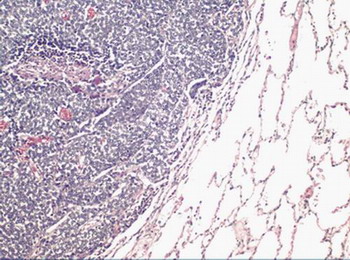

Figura 14 - <div style=fiogf49gjkf0dImagen microscópica de la infiltración neoplásica en el pulmón (HE 100x).">

Figura 14 -

fiogf49gjkf0d

Imagen microscópica de la infiltración neoplásica en el pulmón (HE 100x).

2.- Pulmones: tromboembolismo neoplásico en arteria pulmonar izquierda, que la obstruye totalmente (Figuras 12 y 13 ). Implantes neoplásicos de similares características a las descritas en región lumbosacra, difusamente distribuidos en lóbulo superior izquierdo y los tres derechos (Figuras 14 y 15). En lóbulo inferior izquierdo, neumonía en resolución, con ocupación de la luz alveolar por células mononucleadas, abundantes macrófagos y edema.